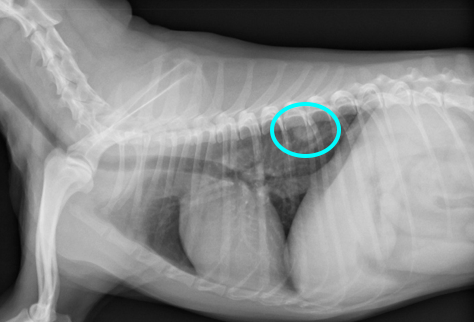

レントゲン検査により偶発的に腫瘤を確認しました。

また、この時に咳などの呼吸器症状は認めていません。

レントゲン検査所見より肺腫瘤を疑い、CT撮影検査と超音波ガイド下での経皮的針生検を麻酔下で同時に行ないました。

画像中央肺野に腫瘤が確認されます。